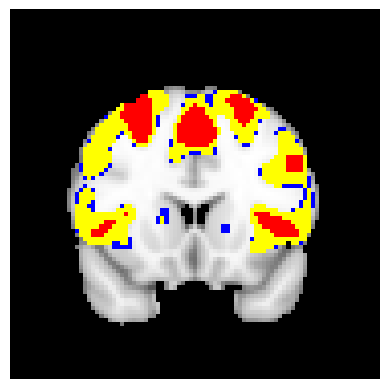

The confidence regions are constructed on fMRI scans from 77 subjects as a real data application of the proposed methods after applying additional smoothing with Gaussian kernel with FWHM to match the results shown in Bowring (2019) [BOWRING2019116187]. Confidence regions using 1) the joint method with , 2) the separate method with BH adjustment for upper and lower side each with , 3) the separate method with BH adjustment for upper side and two-stage adaptive procedure for lower with , and 4) SSS () were compared with threshold level 1.0%, 1.5%, and 2.0% Blood Oxygenation Level Dependent (BOLD) change. Joint control confidence regions are produced with instead of 0.05 for the reasons mentioned in chapter 3.

For all slices, FDR controlling methods show tighter inference of both upper and lower CR compared to the SSS method. SSS shows smaller upper CR and larger lower CR which suggests more conservative inference compared to FDR controlling testing based methodologies. This is due to the fact that by controlling for FDR, the method allows for more false discoveries in exchange for more discoveries in general. Despite having higher level at , joint control confidence regions still show comparable results to other methods even with higher significance level. Naturally, as the threshold goes up, the area enclosed between the upper and lower confidence regions decreases.

Confidence regions with separate controls of FDR for lower and upper are presented in two forms for comparison: one with BH procedure for the lower confidence region, and the other one with the two-stage adaptive procedure for the lower confidence region. The upper confidence region remains the same as both methods uses BH procedure for the upper set FDR control. Lower confidence regions with adaptive method are smaller than lower sets with BH procedure which is to be expected as the two-stage adaptive procedure is less conservative when more voxels are thought to be rejected. In the context of negative one-sided testing, this is equivalent to when there are less number of voxels above than below .